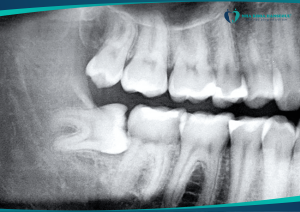

Có nên nhổ răng số 8 khi đang niềng răng?